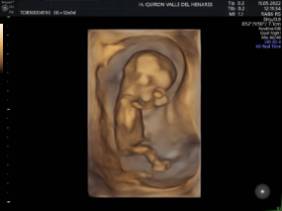

El Hospital Quirónsalud Valle del Henares incorpora un nuevo ecógrafo con tecnología 5 D

El Hospital Quirónsalud Valle del Henares ofrece la posibilidad de realizar ecografías gestacionales 5D. Este tipo de exploración permite obtener una imagen muy realista del bebé y se puede realizar en cualquier etapa de la gestación -aunque lo recomendado es realizarla entre las semanas 28 y 32 de gestación, ya que técnicamente es el mejor momento y es mucho más probable obtener imágenes de buena calidad-.

Al final de la prueba, se entrega a la familia un informe de la ecografía y un soporte digital que contiene las imágenes y los vídeos realizados. Las ecografías 4D y 5D son también llamadas emocionales por la explosión de sensaciones que genera cuando la madre ve por primera vez la imagen del bebé que espera.